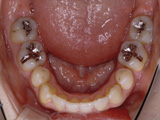

症例6:舌側矯正(見えない矯正治療)

治療前

治療途中

治療後